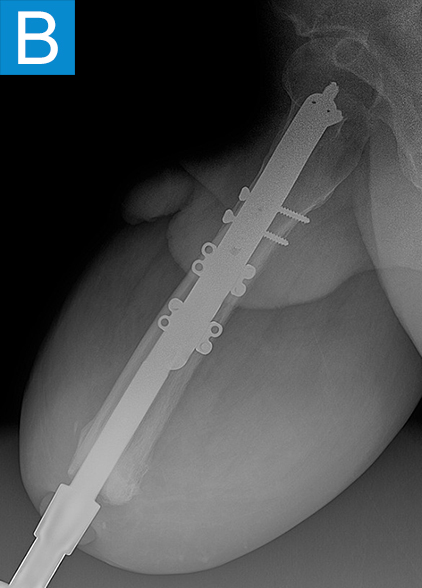

He started progressively loading the implant at 2 weeks and received his full prosthetic leg with simple hinged knee at 6 weeks. At 3 months he no longer used assist devices and at 3.5 months his prosthesis was changed to a microprocessor-controlled knee. Shortly after receiving the new knee, he stumbled stepping over a ledge and fell, sustaining a subtrochanteric proximal femur fracture (Figure 2b). The fracture extended to the tip of the implant, which remained stable in the bone. He underwent open reduction and internal fixation of the femur fracture with a proximal locking plate (Figure 2c). He did not wear the prosthetic leg for 10 weeks, when he began gradually loading the femur. He resumed full weightbearing without assistive devices about 6 weeks later.

Figure 2. Postoperative X-rays shows (A) a femoral osseointegration implant; (B) a subtrochanteric proximal fracture; (C) the femur fracture repaired by open reduction and internal fixation with a proximal locking plate.

Periprosthetic fracture around osseointegrated stems is not surprising, given the stress concentration that occurs proximally to the stem. The incidence is around 5% and mostly due to falls [2]. The stems themselves are nearly always stable in the bone because the osseointegration is robust. This was true in this patient despite less than 4 months of integration time. Thus, the stem can nearly always be maintained and the fracture fixation follows familiar principles. Many periarticular plating options now exist for the femur so that screws can be placed into the diaphysis around the stem to achieve proximal fixation. With stable fixation the healing is usually routine because the forces on the fracture are minimal without the prosthesis attached. Patients usually go back to their prior level of function once healed [2].